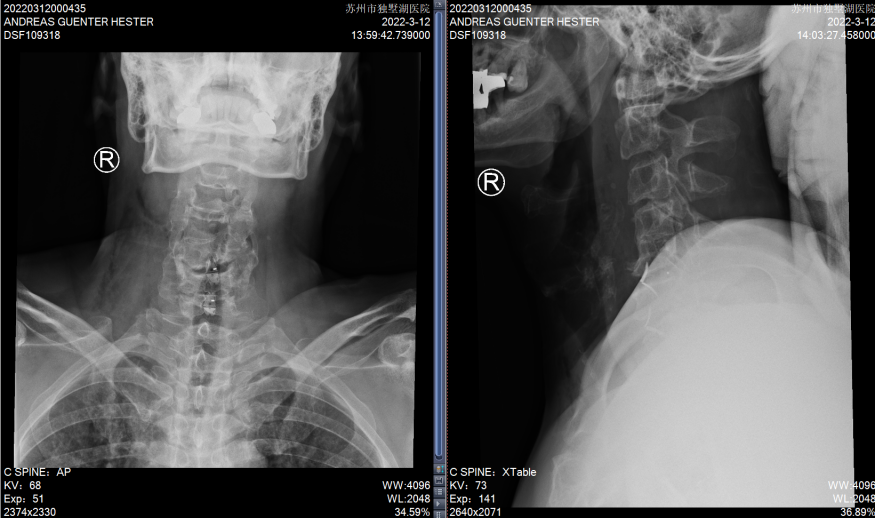

患者C4和C5椎体发育异常

C5/6、C6/7椎间盘突出明显,椎管狭窄,脊髓受压严重

术后复查X片,C5/6和C6/7椎间隙高度恢复满意